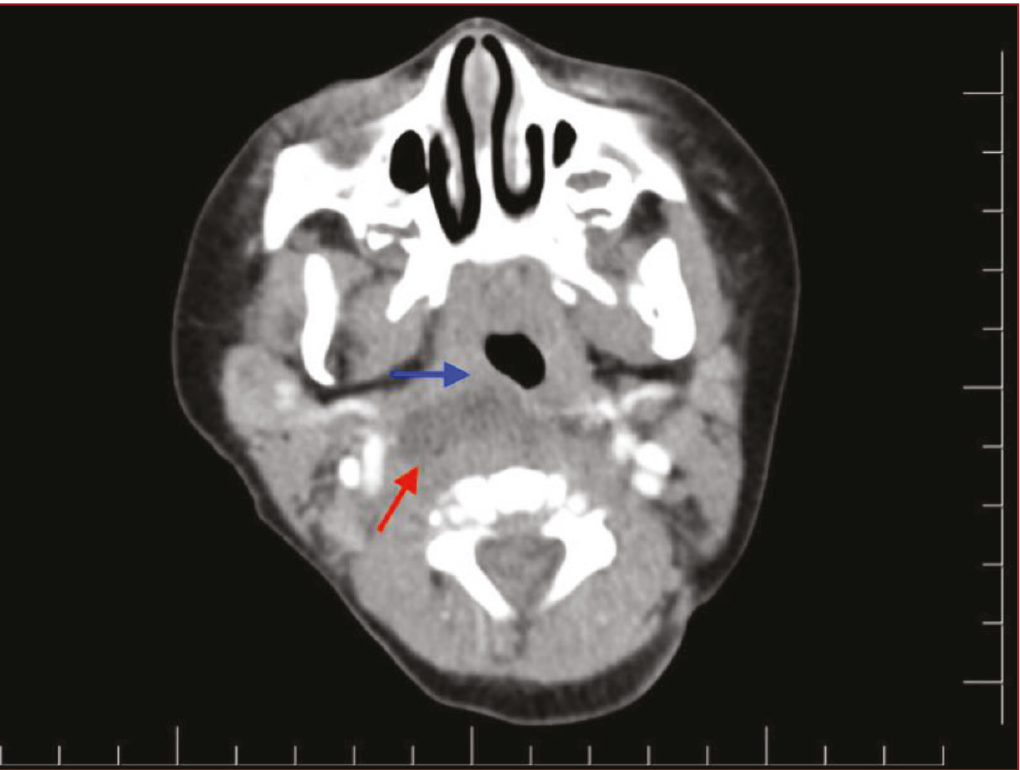

The retropharyngeal abscess (RPA) is an uncommon and potentially fatal infection of the deep spaces in the neck. The global incidence is unknown, but it has been reported to be more common in children between six months and six years. The clinical manifestations are unspecified and exhibit a different disease etiology from those in adults. The imaging studies are useful to reveal details of the severity of the illness and its complications. Treatment options include conservative therapies or surgery. We presented the difficult diagnostic case of a 6-month-old male infant with nonspecific symptoms, and an imaging study that showed a RPA that did not respond to initial antibiotic therapy. Knowledge of clinical manifestations, primary diagnosis tools, and timely treatment of this entity is crucial to avoiding life-threatening complications, especially in infants, given the diagnostic challenge posed by the difficulty of identifying symptoms in this population.